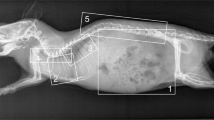

µtarget and µref denote the mean of signal in a certain region of interest (ROI) at the target structure and the reference (ref) tissue, respectively. \(\sigma\) target, \(\sigma\) ref and \(\sigma\) bg represent the standard deviation of the according signal in the ROI of the target structure and reference tissue and background region (bg), respectively. The ROI were manually chosen areas of 64 × 64 pixels. For the background region the ROI was placed outside the object. Target structure was primarily trabecular bone, reference tissue was the soft tissue mantle. No ROI were placed in regions with superposition with other materials (Fig. 8).